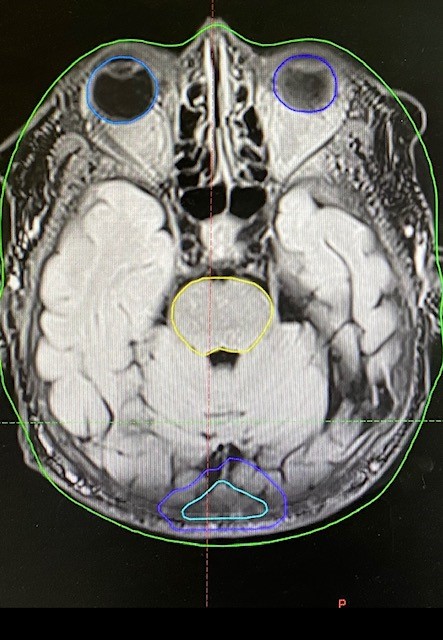

После проведения МРТ-топометрии и определения мишеней с врачом МРТ-кабинета, пациентке по согласованию с Зав.РО№3 и консилиумом радиотерапевтов экспертной группы было решено выполнить лучевое лечение, с учетом небольших размеров мтс, в режиме СТЛТ на пораженные участки костей черепа в правой и левой лобной области, а также ложе мтс кости затылочной области(после опер. лечения).

Данное лечение заняло 5 койко-дней, составляло 3 фракции с РОД8Гр, СОД24Гр .